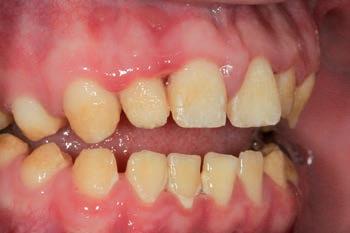

On clinical examination, UR1 was responsive to viability testing, and did not present periapical lesions on the radiograph performed on the same day (Figure 1). UR1 was discoloured and in a more palatal position than the contralateral central UL1 (Figure 2). The aesthetic analysis highlighted an asymmetry of the gingival zenith between UR1 and UL1. Through the use of a periodontal probe, after plexus anaesthesia, the altered passive eruption of the type IA junctional epithelium was confirmed according to the classification of Coslet et al. (Figure 3).

FIGURE 2: Discolouration and palatal position of UR1.

FIGURE 3: The aesthetic analysis shows an asymmetry of the gingival zenith.